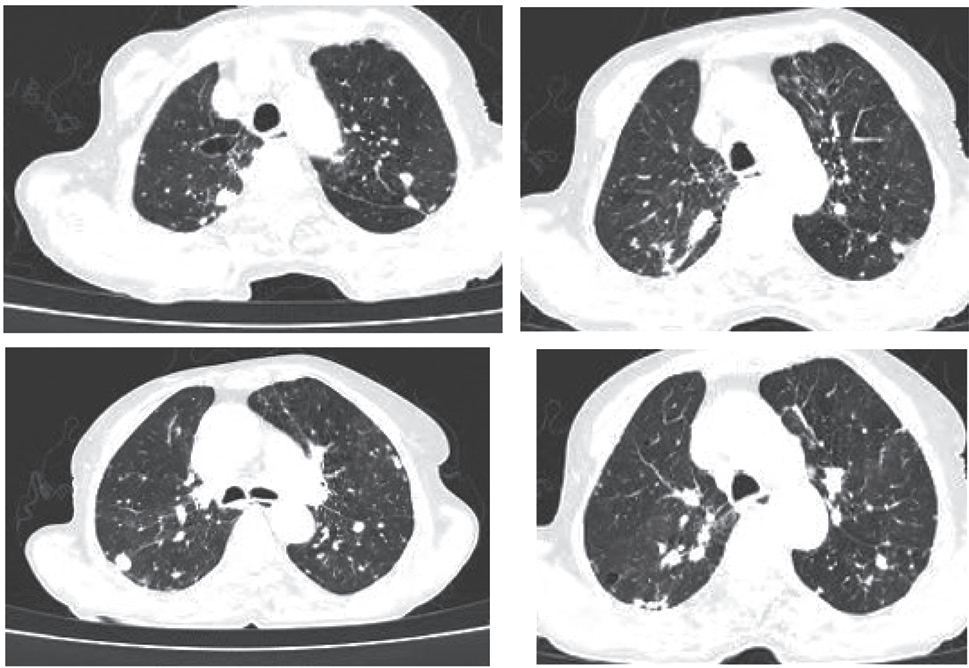

结核病好发部位为上叶尖段和下叶背段,其病变以结节影、斑片及小斑片样实变影为主 [9](图 3);肺炎患者 CT 影像显示新出现的斑片状浸润影、叶或段实变影、磨玻璃影或间质性改变 [10](图 4)。肺结核由结核杆菌引起,病理特征为结核结节、干酪样坏死等,早期炎症渗出与肺炎的肺泡内炎性渗出在影像学上难以区分。肺炎由细菌、病毒等感染所致,病理以肺泡实变为主,若病变范围小或不典型,也易与肺结核混淆。

注:患者男,60 岁,双肺上叶及下叶背段多发小结节影,右肺上叶后段斑片状致密影。

图 3 肺结核患者 CT 扫描图像